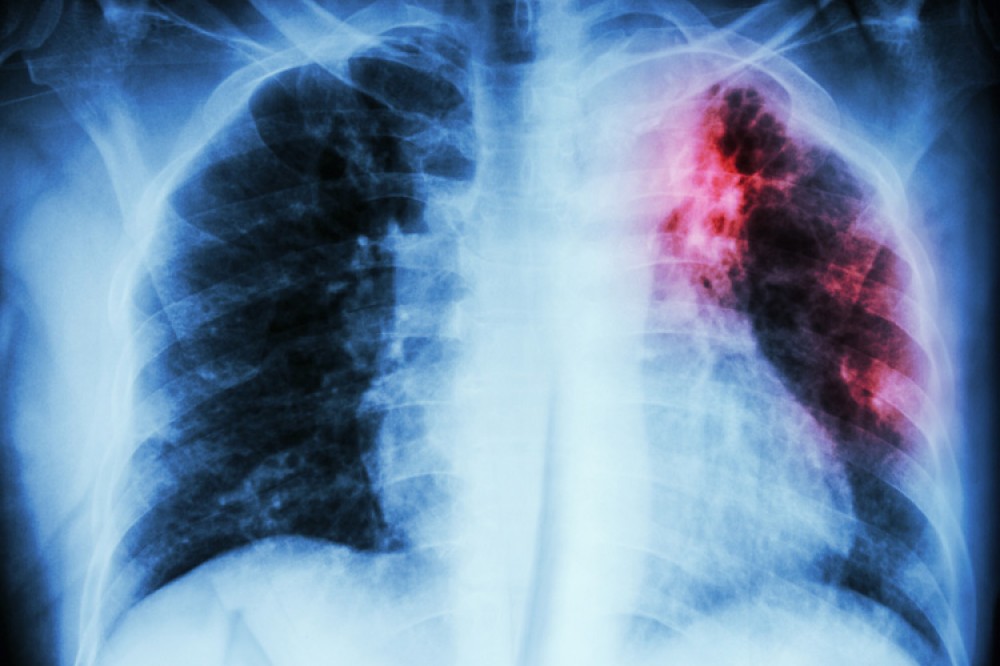

Vərəm kimi tanınan tuberkulyoz hələ də ciddi sağlamlıq problemi olaraq qalır, lakin mütəxəssislər bildirir ki, ondan qorunmaq üçün mürəkkəb və bahalı üsullara ehtiyac yoxdur. Sadə həyat tərzi dəyişiklikləri ilə bu riski əhəmiyyətli dərəcədə azaltmaq mümkündür.